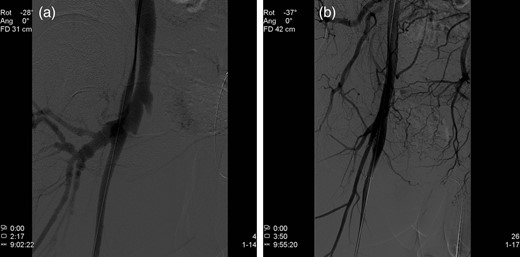

Endovascular treatment of the AV fistula was performed in the following day. The contralateral femoral artery was accessed, angiography showed the fistula (Fig. 2a) and a stent-graft (Fluency, Tempe AZ, USA) was implanted in the cranial part of the right superficial femoral artery, covering the fistula (Fig. 2b). Treatment eliminated the arterial phase contrast filling in the veins. The patient recovered rapidly and was discharged 1 month later, after a total hospital stay of almost 8 weeks. Intravenous antibiotic treatment (cloxacillin and ciprofloxacin) continued until discharge. After discharge, he received oral trimethoprim sulfamethoxazole for another 4 weeks. At last follow-up, he showed no signs of recurrent infections, but was still intermittently abusing drugs.

(a) Angiography demonstrating an AV fistula between the right superficial femoral artery and the femoral vein. (b) A stent-graft is implanted in the cranial part of the right superficial femoral artery, sealing the AV fistula.